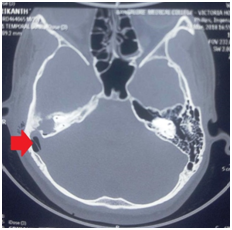

A 20 years old boy was admitted to our hospital with history of intermittent ear discharge which was foul smelling and occasionally blood stained with ear pain since 3yrs of his age. He had history of reduced hearing from past 10 yrs. From past 20 days he had developed above complaints along with fever, vomiting, and neck swelling with pain. On examination, he was febrile, conscious oriented and ill looking. Otological examination revealed, purulent discharge from right ear canal with granulation tissue which obscured the view of tympanic membrane. He had tenderness and oedema over right mastoid region and had conductive deafness. He also had tenderness with diffuse swelling over right side of his neck and torticollis (Figure 1). Rest of the examination was normal. There were also features suggestive of right internal jugular vein thrombosis. Computed tomography (CT) scanning at a local hospital revealed features suggestive of chronic suppurative otitis media with lateral sinus thrombophlebitis. He was then transferred to our hospital for further evaluation and management. Repeat HRCT temporal bone revealed, feature suggestive of right coalescent otomastoiditis causing, sigmoid sinus plate and tegmen tympani erosion causing thrombosis of right transverse, sigmoid sinus and internal jugular vein with subcutaneous abscess with pnemocephalus (Figure 2).

Figure 2 HRCT of the temporal bone showing pnemocephalus [arrow] on the right side.